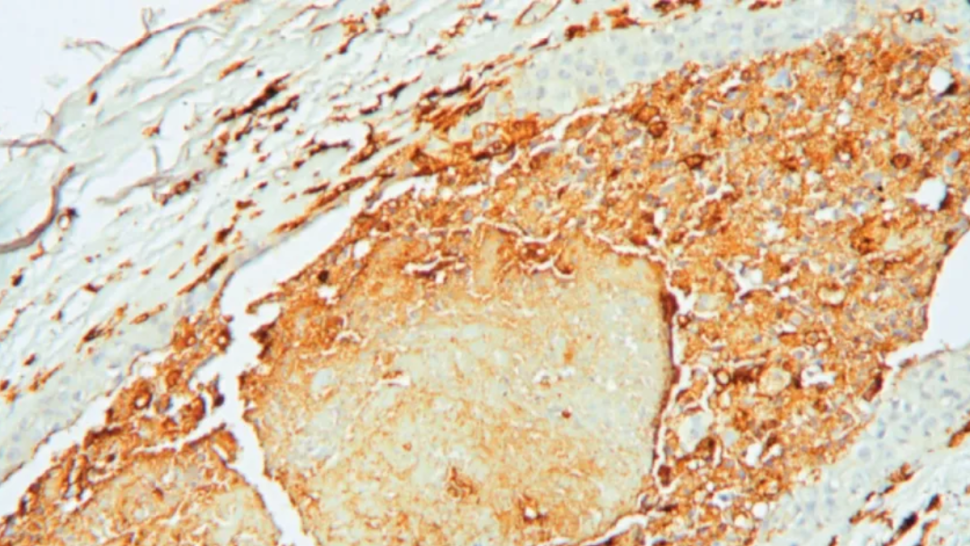

وأظهرت صور مجهرية أن الخلايا العصبية في هذه المنطقة تدخل في حالة فرط نشاط مستمر، لكنها في الوقت نفسه تنتج مخرجات هرمونية ضعيفة، ما يجعلها في حالة "تشغيل دائم" فاقدة للإيقاع الطبيعي.